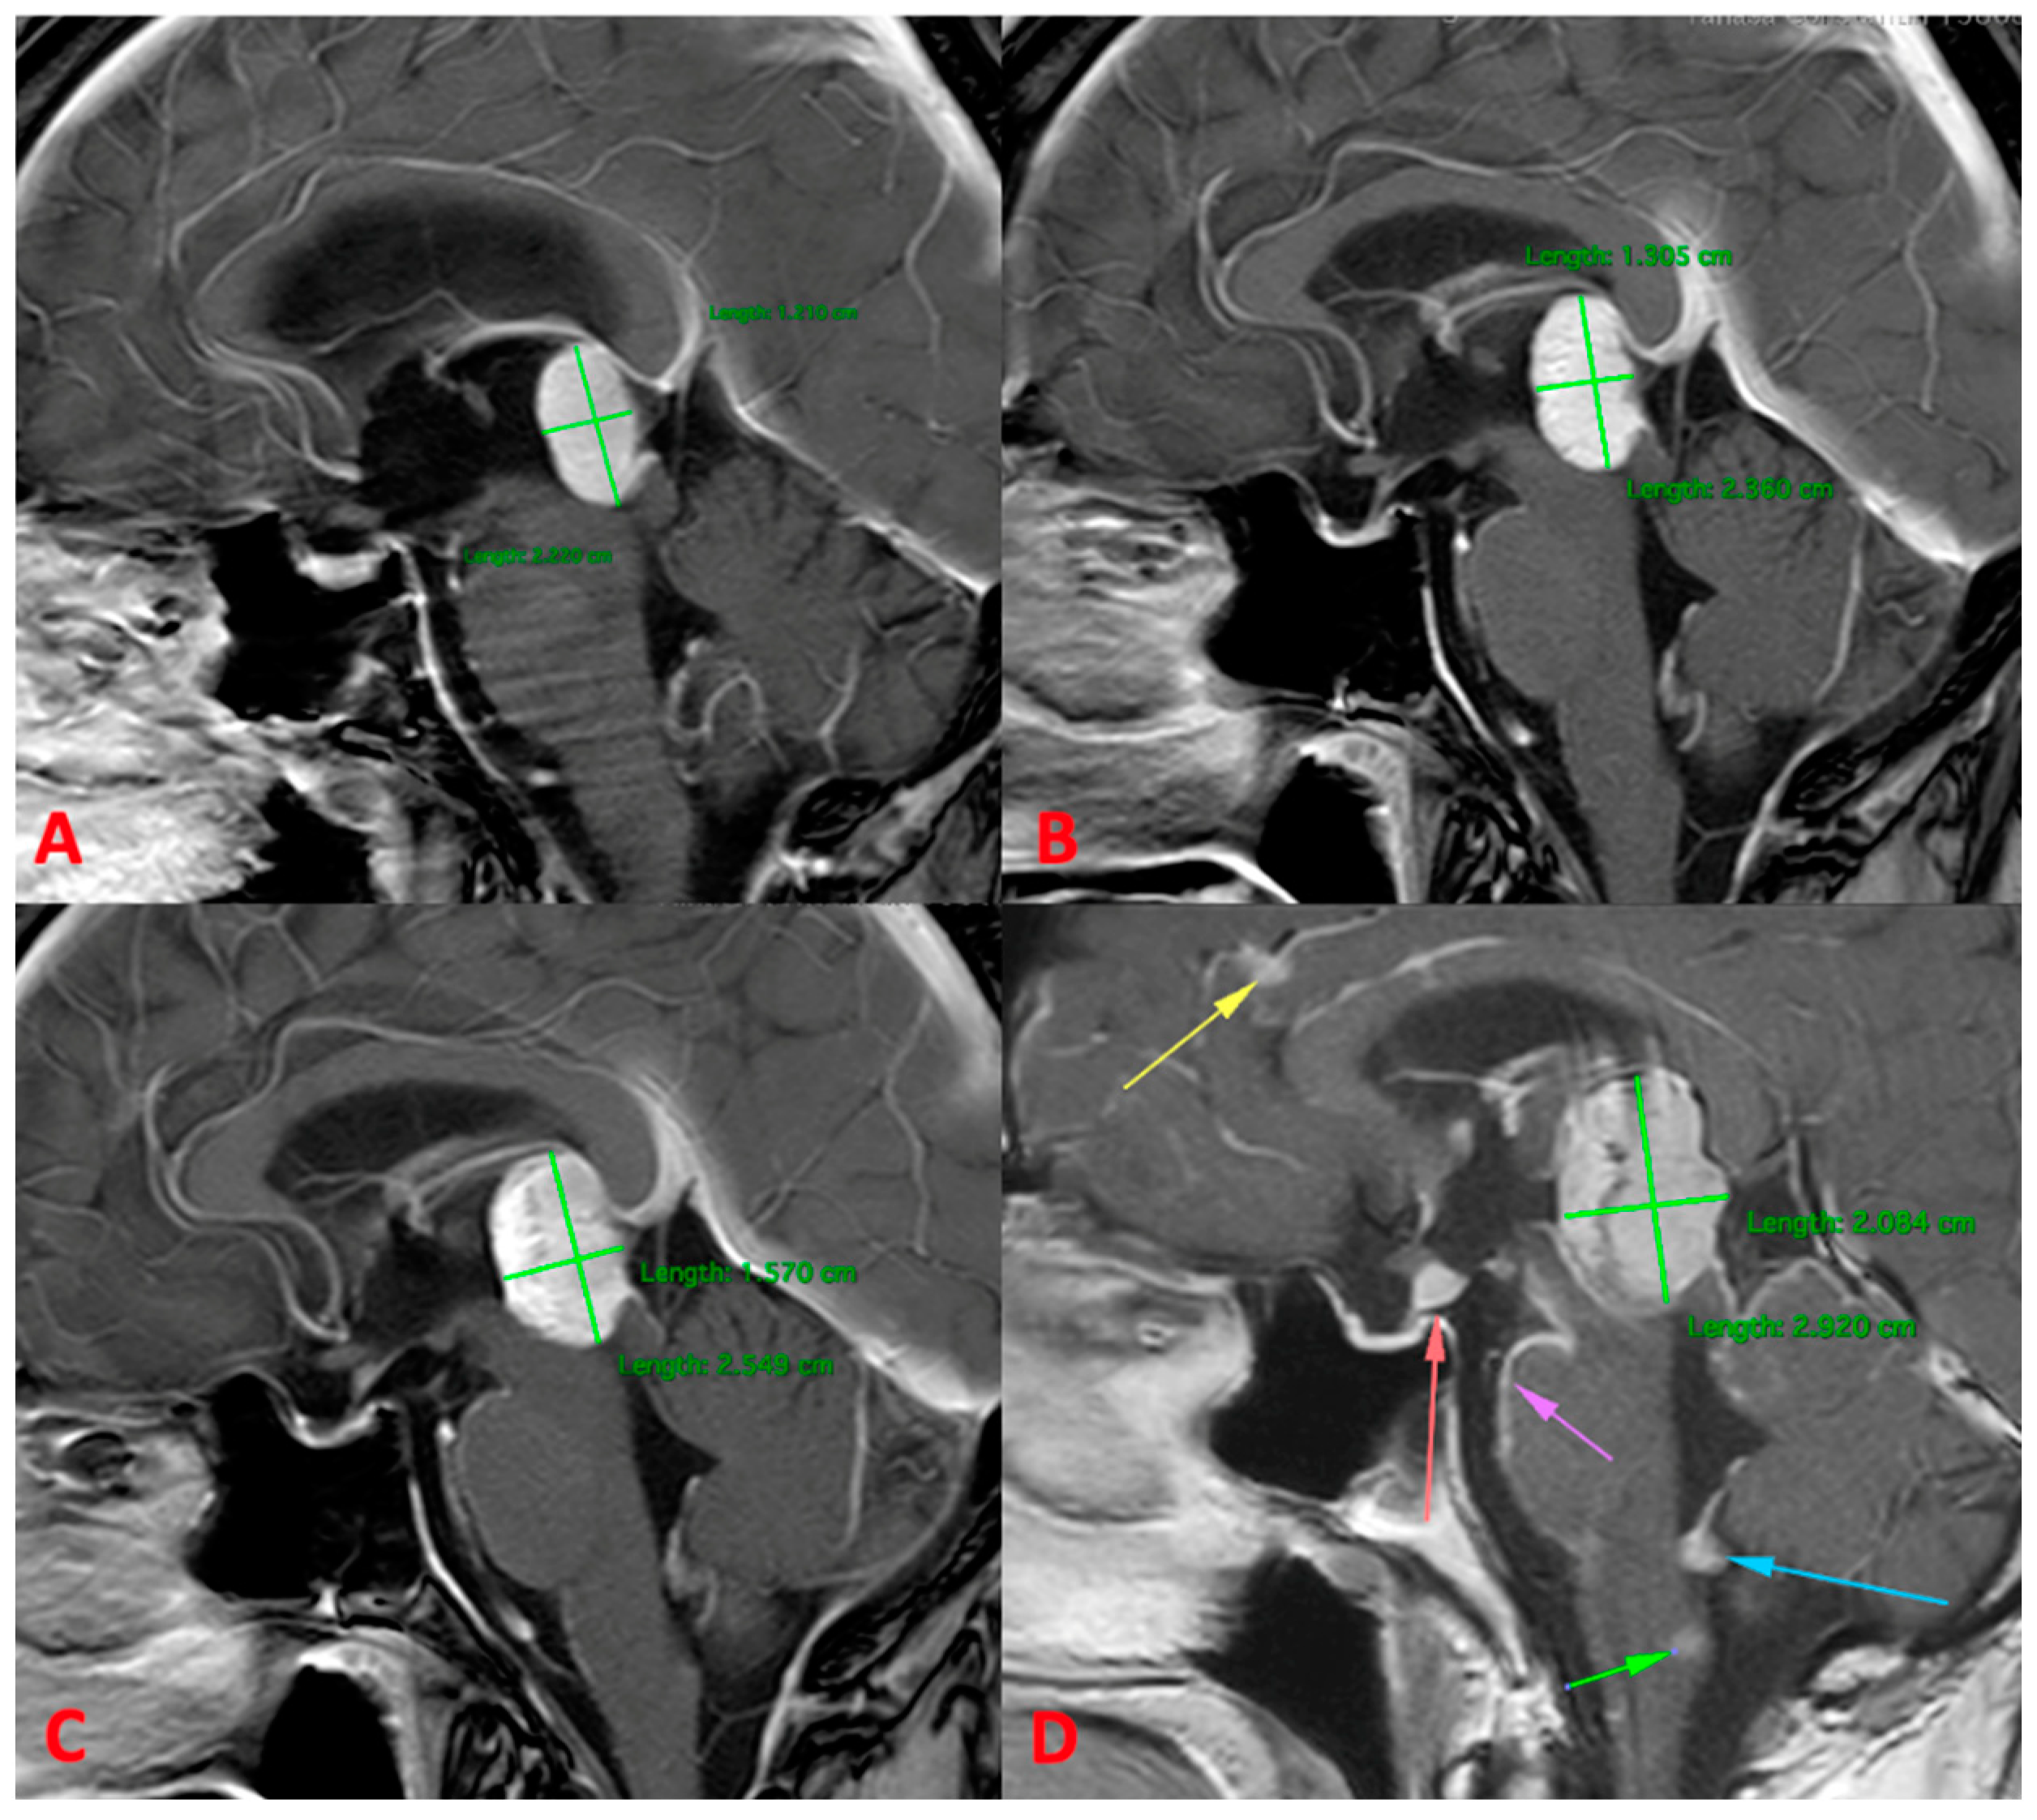

3.2.2. MRI